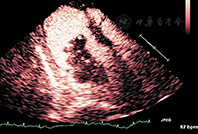

④左心室心尖血栓:心尖是左心室血栓最常见发有助于明确诊断,可用实时超低MI灌注成像以及高MI"闪烁"成像鉴别血栓与肿瘤。如无实时超低MI成像软件,可使用低MI谐波成像。血栓显示为典型的心腔内充盈缺损,血栓内无造影剂回声[29,30,31] (图8)。偶尔,心腔内血栓呈白色强回声,如果造影显像使用灰度显示,血栓高强度回声可能混入白色不透明的左心室血池中而影响识别,此时使用能量谐波多普勒成像可能更有利于血栓的识别。